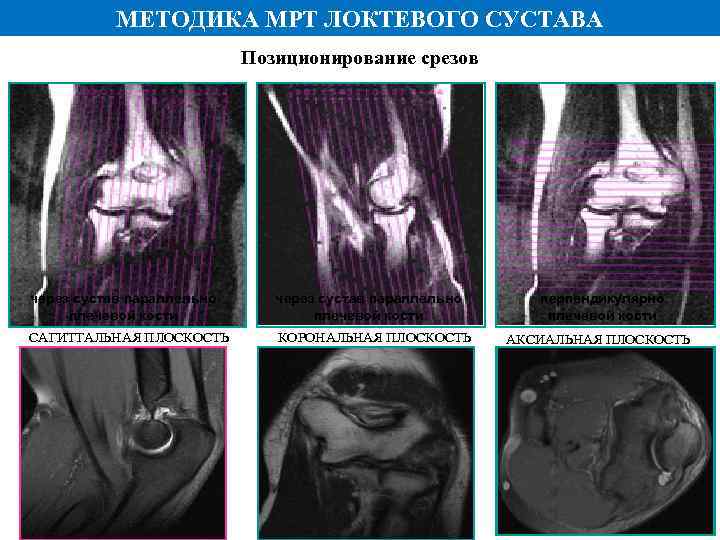

МЕТОДИКА МРТ ЛОКТЕВОГО СУСТАВА • Специальная поверхностная катушка • Положение пациента – лежа на животе • Верхняя конечность в нейтральном положении • Получение изображений в трех стандартных для локтевого сустава плоскостях – корональной, сагиттальной и аксиальной • Оптимальные последовательности – Т 1, Т 2, Pd и Pd-Fs (жироподавление)

МЕТОДИКА МРТ ЛОКТЕВОГО СУСТАВА • Специальная поверхностная катушка • Положение пациента – лежа на животе • Верхняя конечность в нейтральном положении • Получение изображений в трех стандартных для локтевого сустава плоскостях – корональной, сагиттальной и аксиальной • Оптимальные последовательности – Т 1, Т 2, Pd и Pd-Fs (жироподавление)

МЕТОДИКА МРТ ЛОКТЕВОГО СУСТАВА Позиционирование срезов через сустав параллельно плечевой кости САГИТТАЛЬНАЯ ПЛОСКОСТЬ КОРОНАЛЬНАЯ ПЛОСКОСТЬ перпендикулярно плечевой кости АКСИАЛЬНАЯ ПЛОСКОСТЬ

МЕТОДИКА МРТ ЛОКТЕВОГО СУСТАВА Позиционирование срезов через сустав параллельно плечевой кости САГИТТАЛЬНАЯ ПЛОСКОСТЬ КОРОНАЛЬНАЯ ПЛОСКОСТЬ перпендикулярно плечевой кости АКСИАЛЬНАЯ ПЛОСКОСТЬ